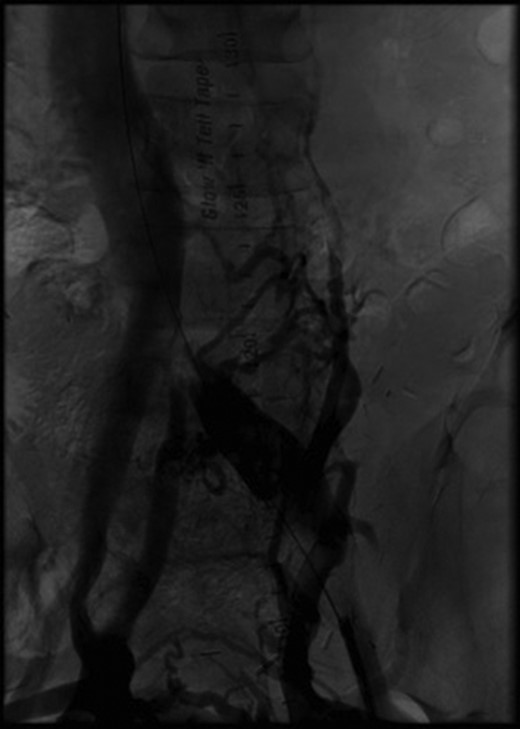

Initial angiography demonstrating thrombus in left common iliac vein with surrounding collaterals.

Two months after her transplant she developed abdominal pain and a CT scan was performed. Imaging demonstrated an extensive thrombus in the left common and external iliac veins, with compression of the left common iliac vein superior to the thrombus (Fig. 2). An interventional cardiology team performed angiography which showed a 100% occlusive lesion in the left CIV, with thrombotic defect in the left EIV, and patent pancreatic SMV and left renal vein. Balloon angioplasty and combined Angiojet and manual thrombectomy of the left common and external iliac veins was performed. A 16 mm x 40 mm Wallstent self-expanding metal stent was deployed in the left CIV, with a proximal landing site in the IVC, just distal to the pancreatic vein graft. Post-procedure angiography demonstrated a 30% residual stenosis, with patent flow through the LCIV and LEIV, and both the pancreatic and renal grafts. She was started on therapeutic anticoagulation after the procedure. Surveillance imaging 6-months post-procedure demonstrated no residual clot burden and appropriate stent positioning. Labs at 1 year follow up show persevered allograft function, with creatinine 0.91, amylase 88 and lipase 140, and no insulin requirements.